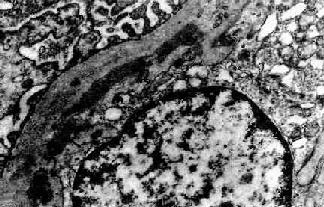

图12-15 膜性增生性肾小球肾炎 Ⅰ型

肾小球毛细血管基底膜内侧,内皮细胞下电子致密沉积物,部分上皮细胞足突消失